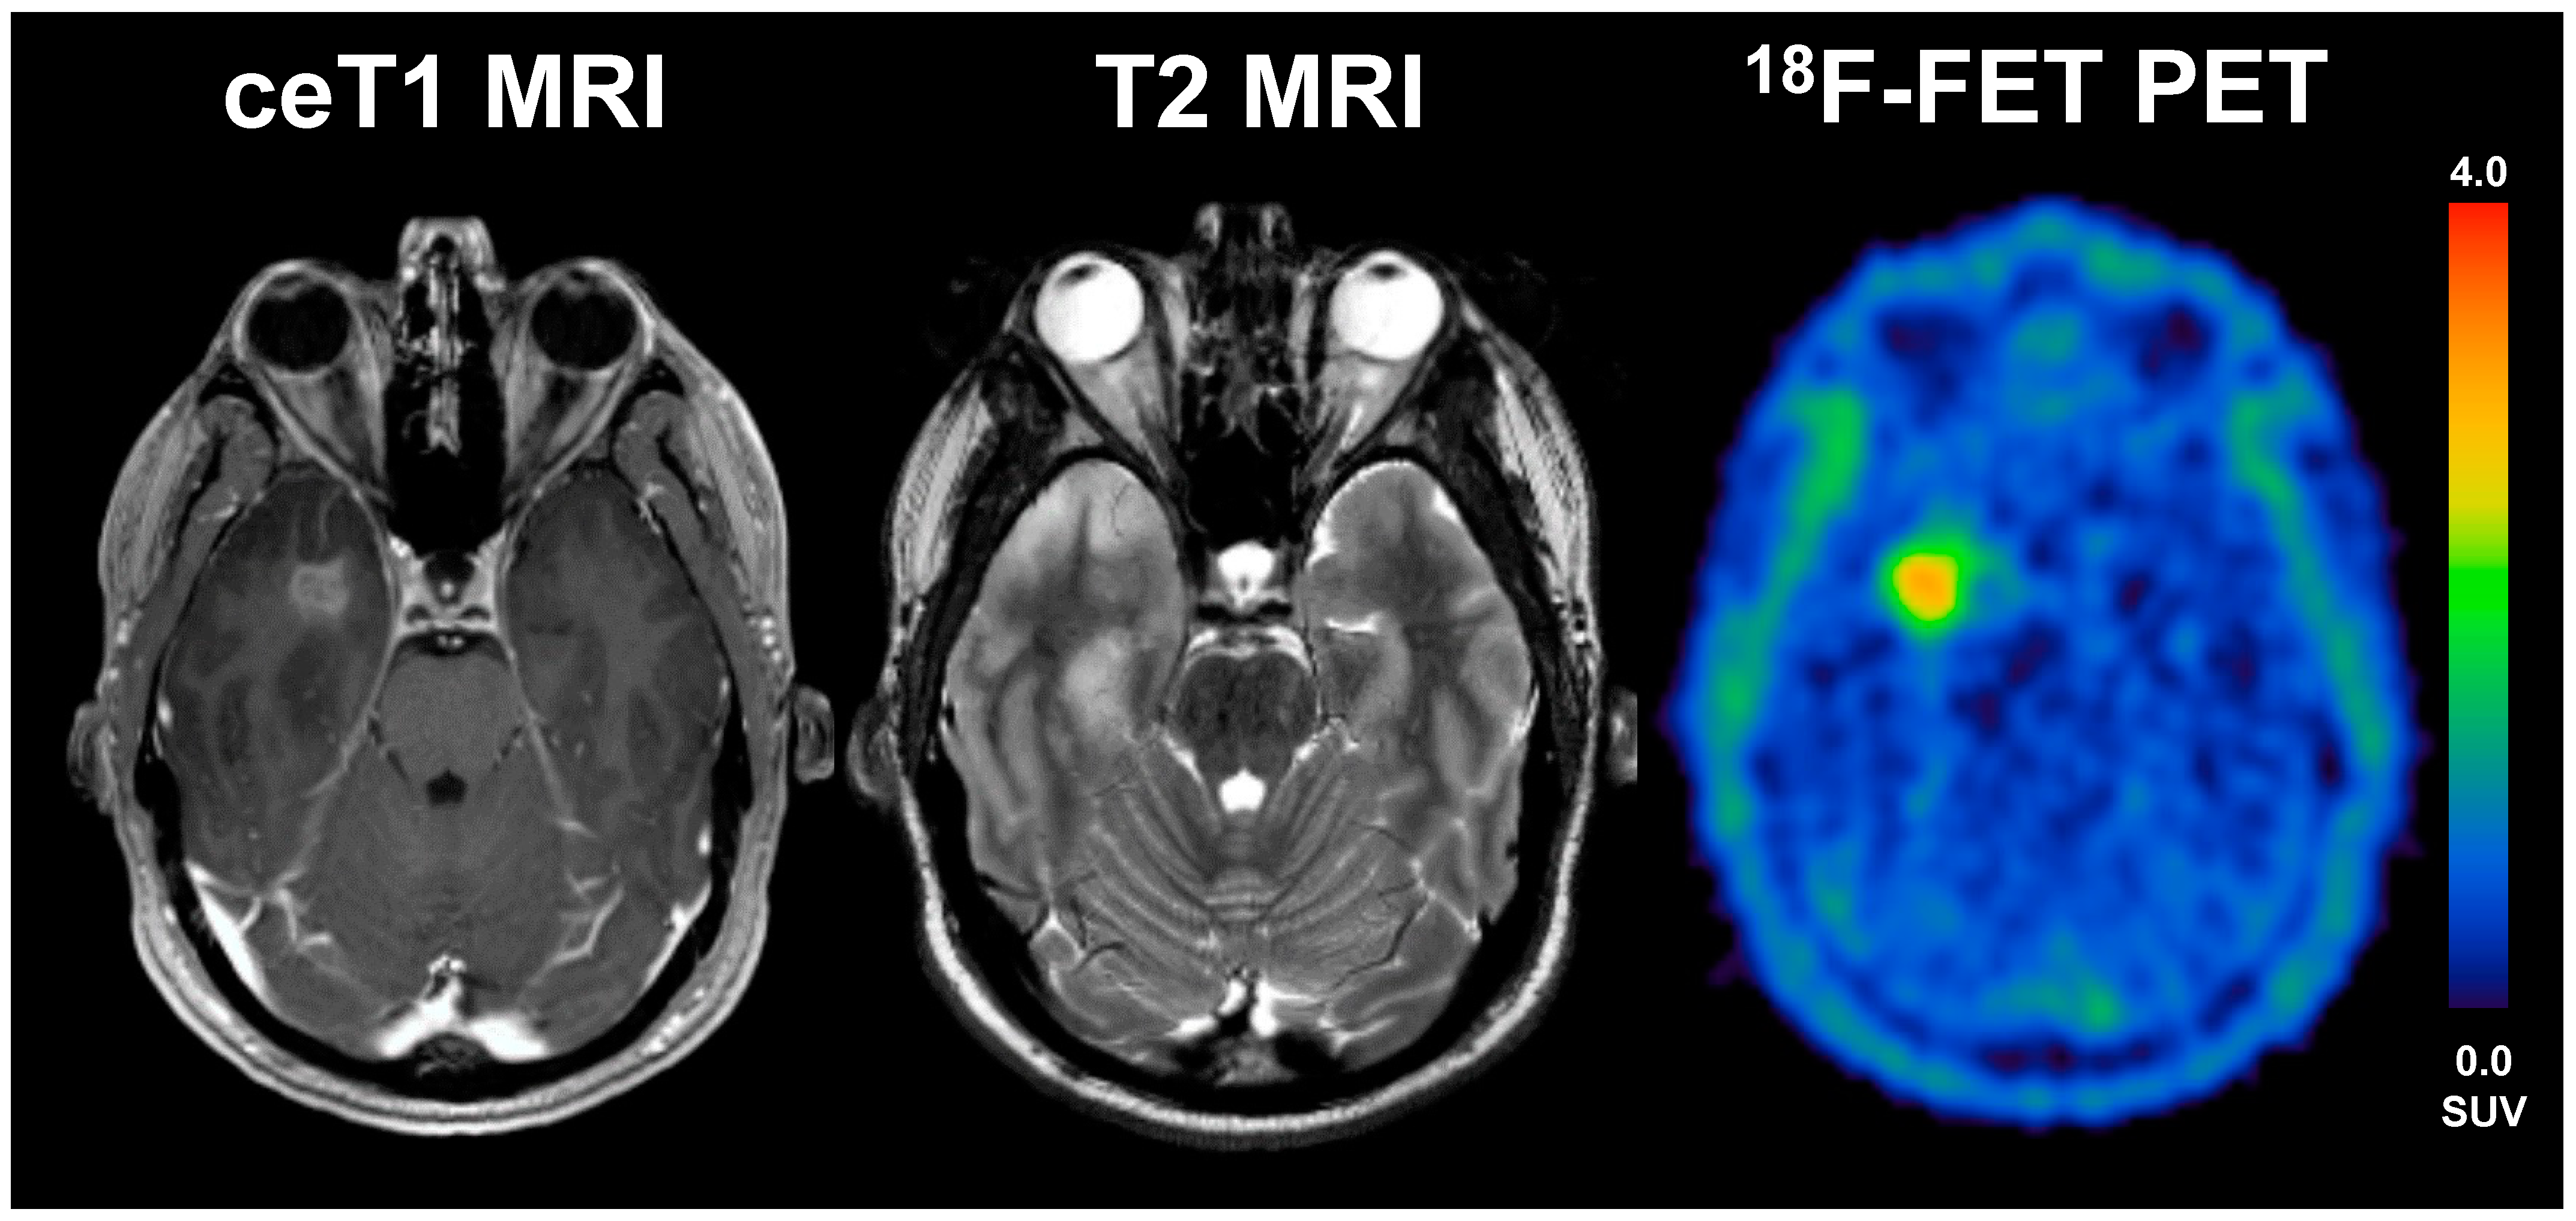

Figure 3.

A 33-year old male patient with glioblastoma (WHO grade IV, IDH wildtype, MGMT methylated) and an overall survival of 47 months (LTS). The diameter of CE on T1 MRI was 17 mm, volume of CE was 28 mL, the BTV in FET-PET was 16 mL, the TTPmin was 17.5 min and TBRmax 4.1. The patient underwent radio-chemotherapy.